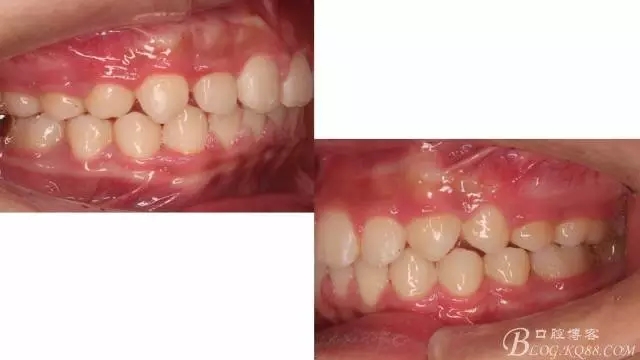

一晃快兩年了,我覺得關節(jié)重建及咬合穩(wěn)定,再加上患者的急迫愿望,我們拆除了矯正器。

尖牙關系中性,磨牙關系中性,咬合鎖結(jié)良好!